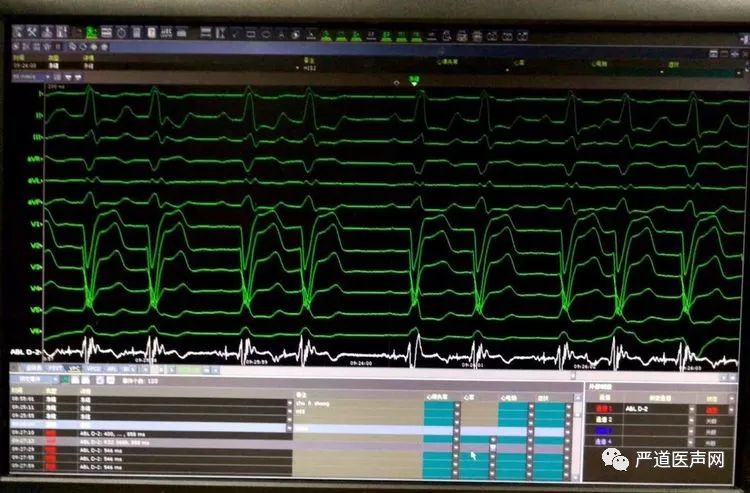

左束支起搏大致操作过程: 1.记录到希氏束电位:2.起搏观察希氏束起搏电图,看是否能够纠正LBBB。从图二可以看出,该患者希氏束稍虽然能改善LBBB,但QRS仍然较宽:3.记录到右束支电位:4.高电压起搏右束支,观察是否出现LBBB消失,QRS变窄:5.将主动电极旋转使其穿过室间隔,到达左束支区域,并记录到左束支电位:6.测试稍参数,观察LBBB消失及QRS变窄情况:7.植入心房电极,关闭囊袋。

希氏束电位

图二